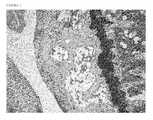

FIG. 1 is a photograph of the histopathology tissue section of a Control Mouse knee (Group A untreated Control Mouse six week post surgery; average score 5.33/24).

FIG. 2 is a photograph of the histopathology tissue section of a Control Mouse knee (Group 13 Saline 3 week Control average score 10.7/24).

FIG. 3 is a photograph of the histopathology tissue section of a Control Mouse knee (Group C Saline 6 week Control average score 12.8/24).

FIG. 4 is a photograph of the histopathology tissue section of a Treatment Mouse knee (Group 1) MBH3™ week Treated average score 7.2/24).

FIG. 5 is a photograph of the histopathology tissue section of a Treatment Mouse knee (Group MBH3™ 6 week Treated average score 7.8/24).

Thirty 10 week old male C57BL/6 mice purchased from Charles River Laboratories were subjected to a meniscotibial ligament transaction surgery of the left knee. This surgery creates a slowly advancing instability condition that mimics the loss of articular cartilage in humans with OA. After six weeks mice were randomly assigned to 5 groups. Group A (Untreated Controls N=6) was cuthanized, their knees decalcified, paraffin embedded, stained with Saffrin-O and scored (Pritzker et al.) to confirm disease onset and cartilage loss. A histopathological score of 1 indicates articular cartilage which is intact and pristine. A score of less than 10 indicates that a great deal of healthy articular cartilage remains. A histopathological score of 24 indicates total loss of articular cartilage as is observed in very severe cases. Following confirmation of cartilage loss at week 6 post surgery Group 13 (Controls. N=6) was gavaged 5 days/week for 3 weeks with saline; Group C (Controls, N6) was gavaged 5 days/week for 6 weeks with saline; Group D (Treated, N=6) was gavaged 5 days/week for 3 weeks with MBH3™ at a dose of 10 mg/kg; and Group E (Treated, N=6) was gavaged 5 days/week for 6 weeks with MBH3™ at a dose of 10 mg/kg. At the end of three weeks of treatment Groups B and D were euthanized, scored and compared. At the end of the six weeks treatment Groups C and E were euthanized, scored, and compared.

The average score of Group A (6 week surgery) was 5.33/24, indicating the onset of osteoarthritis disease and serving as a baseline. The average score in Group B (3 week saline control) was 10.7/24 versus the average score of Group D (3 week MBH3™ treated) was 7.2/24: the average score in Group C (6 week saline control) was 12.8/24 versus the average score of Group E was 7.8/24. The result of this study strongly supports the disease modifying and protective benefits of MBH3™ when used in an established model of osteoarthritis. To our knowledge this is the first time that an orally administered, exogenous hyaluronan biopolymer has been shown to have such benefits.